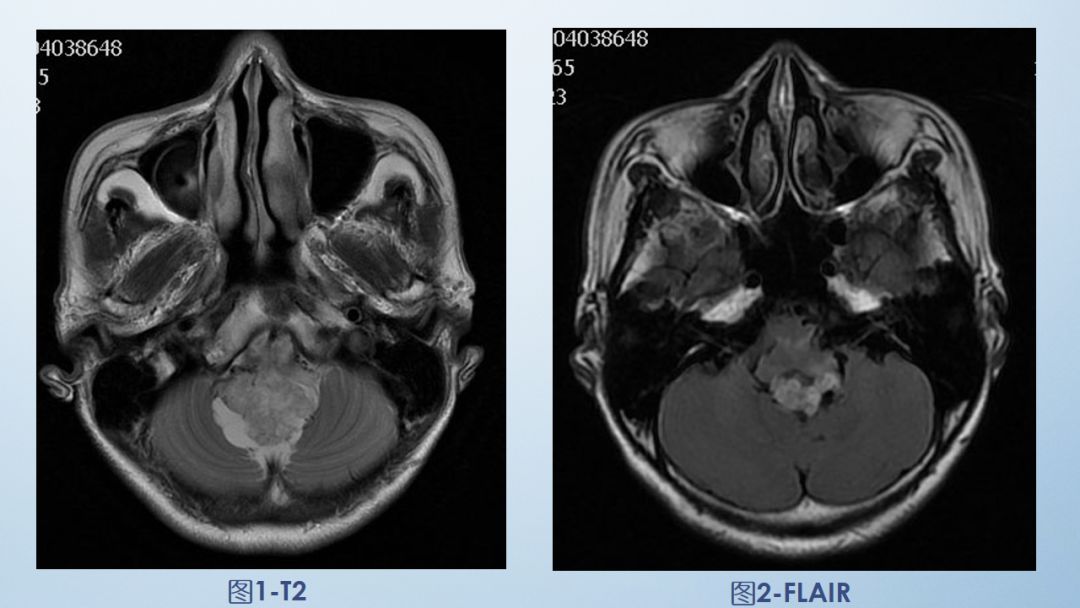

FLAIR图及T1矢状位增强:白色箭头所示小脑延髓池内可见实性占位病变,形态不规则,呈分叶状,病变边界清晰,边缘见血管流空信号影如蓝色箭头所示。

影像描述:小脑延髓池内见不规则异常信号影,呈等及稍长T1长T2信号,内部信号不均,边缘见稍粗大流空信号血管影,FLAIR病灶中心少许片状低信号,增强呈明显强化,DWI不均低信号,ADC不均高信号。小脑半球、延髓、第四脑室受压变形。临近延髓受压变窄,呈长T1长T2信号。

2-FLAIR

6-T1ensag